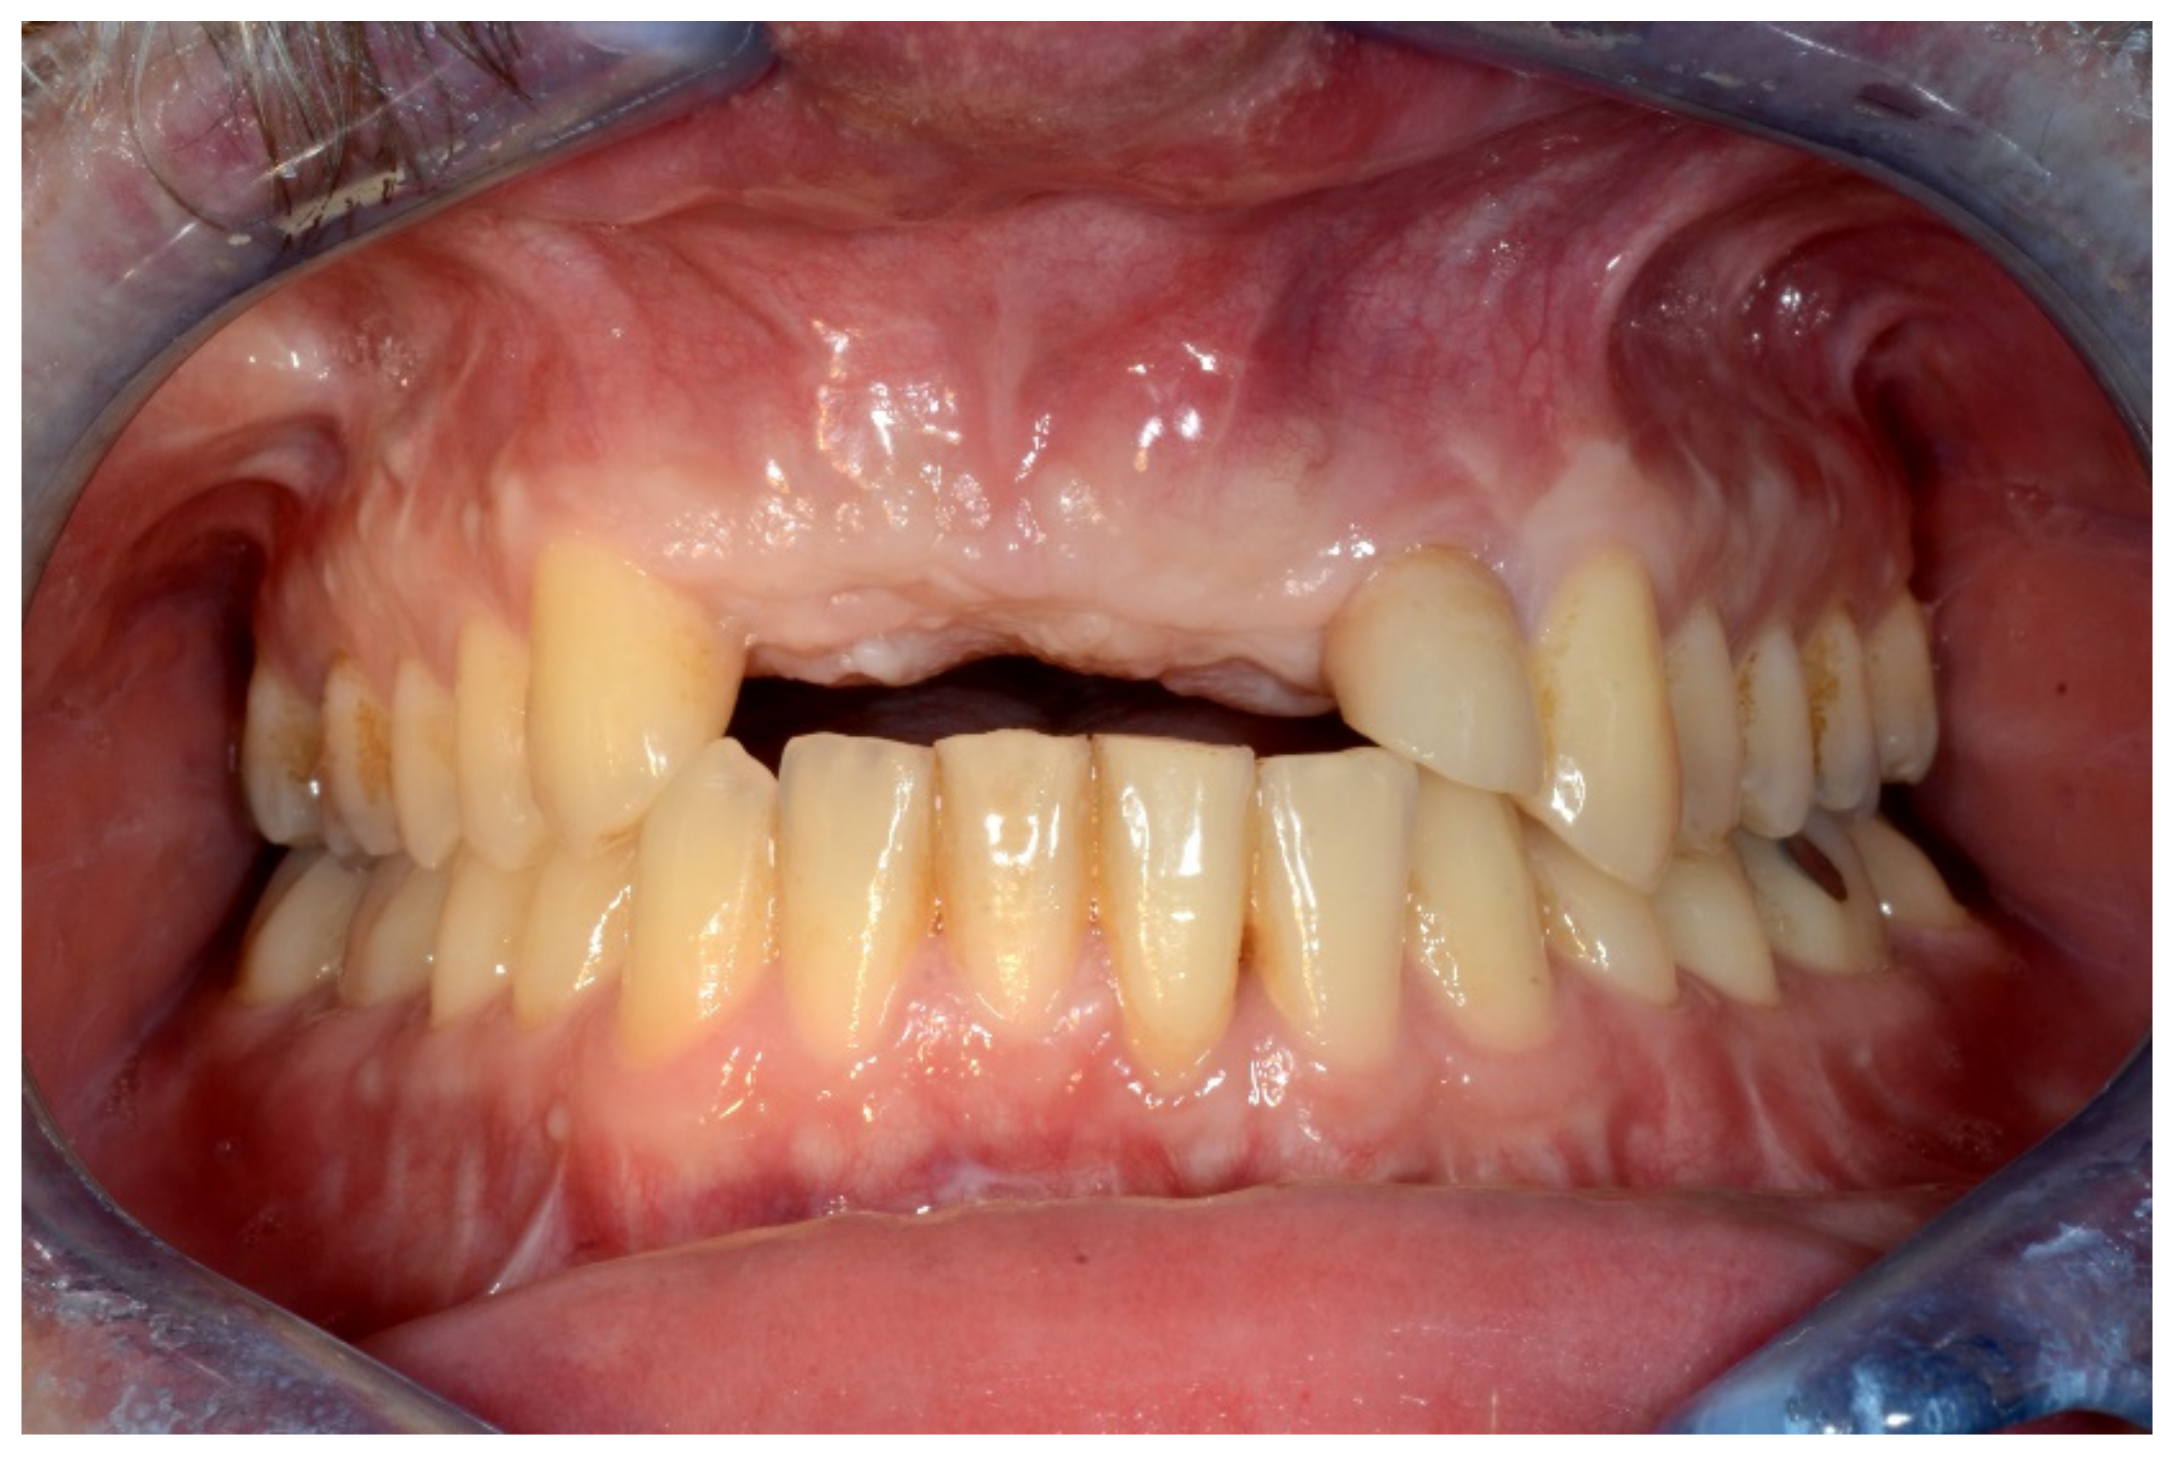

Figure 1.

Frontal view showing the edentulous defect.

Figure 2.

Occlusal intraoral view showing the edentulous defect.